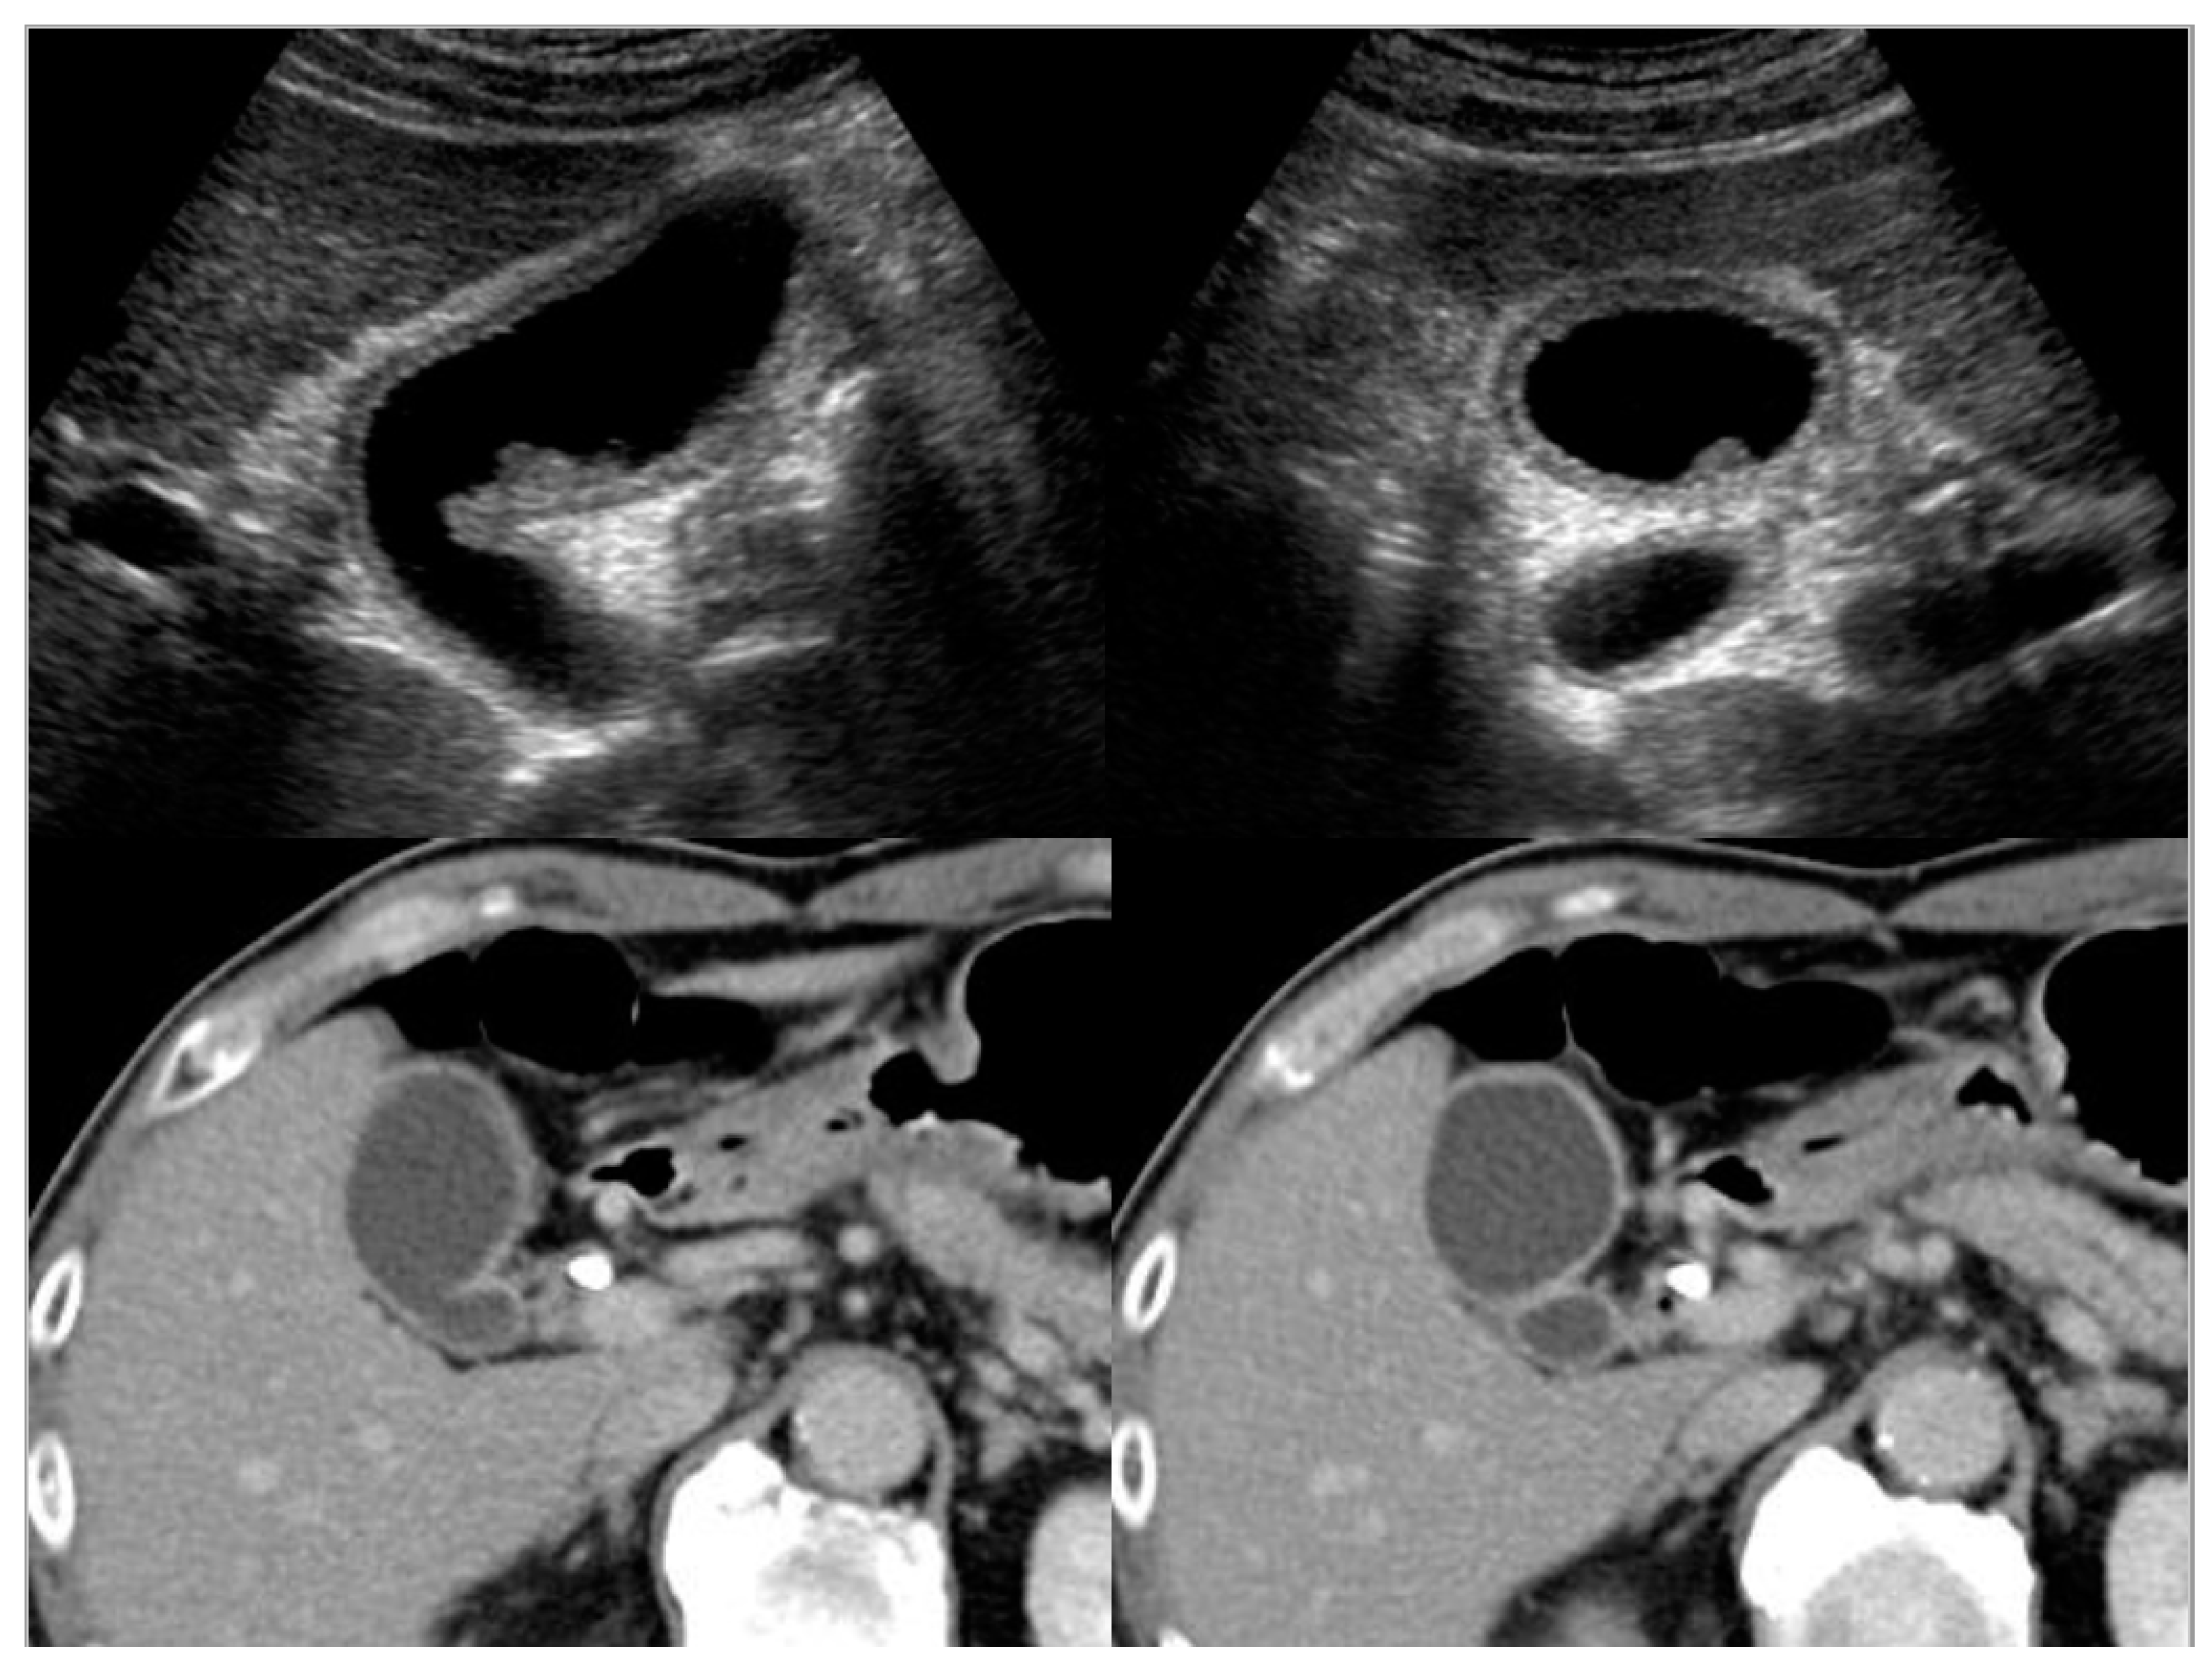

4.1. Diffuse Type of IgG4-CC

4.2. Localized Type of IgG4-CC

5.1. Gallbladder Cancer